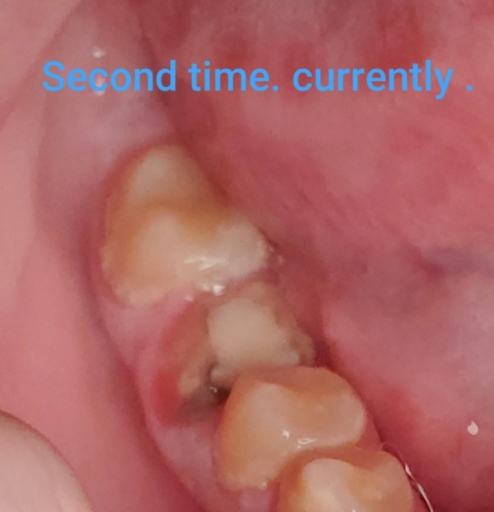

About 2 years ago, while I was in college and I was on Christmas break 2008, I had a root canal procedure in the molar identified as #15. After the procedure, my dentist measured the tooth for the crown and then placed a temporary crown over the shaved tooth. I was supposed to receive the permanent crown, in a month when I return home on another break but the permanent one fell out. The dentist had to shave the tooth down more & also replace two orange rubbery fillings that came out. Two months later, I went back to my dentist to have the permanent crown fitted. When the dentist attempted to put the crown on, it didn\'t fit properly. Two months later (it\'s now summer time, I\'ve graduated from college, and now I am home), I go to the dentist to have the new permanent crown placed. The process is finally completed. Fast Forward to now, 1 &1/2 years later. M In the past three weeks, I experienced a massive amount of pain in the molar where the canal was performed. It started as a a constant throbbing pain all over the head and even in my chest. I had a fever the first day this occurred. Some days the pain goes away but still hurts when pressured is applied. Some days I experience the throbbing pain again. I can\'t eat on those days or even speak. I take advil but it doesn\'t always work. A few nights I have been unable to sleep. It seem laying down only makes the pain worse. I went to another Dentist at NYU School of Dentistry. The students and the professor say an infection is in the canal. I went back to my Dentist so that he too could take an x-ray. The infection was there when he first performed the root canal. But other x-rays show the infection remained even after the root canal was performed. I’m pretty sure it was supposed to be removed during the procedure. I am also pretty sure he was aware it remained but did nothing about it because he wanted me to continue to come so that he could make money off my insurance. When I returned to him yesterday to get xrays, he gave me a prescription for antibiotics & removed my crown so that it will relieve the pressure (“your infection presses down on the tooth as your bottom teeth force the teeth up.”) The crown is damamged and cannot be placed back on. I now have no insurance. I have two deep cavities that must be filled. NYU will charge me $700 to retreat the canal. I have no clue how much the new crown will cost. The fillings at NYU may cost $120 each. (Also, one of the cavities was already filled by my dentist in 2009 and fell out during Summer 2010). I don’t trust my dentist. Also we will probably charge way more. I asked him several times for an estimate concerning the fillings and he consistently attempted to beat around the bush. He also said he may need to perform a root canal on the tooth where the filling came out. NYU said the the cavity is deep but a root canal is not necessary. I have decided to have both fillings done. Now that I have antibiotics, I am considering just having the tooth measured for a new crown without having the root canal procedure redone. What should I do?

I'm sorry you are experiencing such a traumatic time with this tooth. First, after the root canal is performed a permanent crown should be placed as soon as possible to keep the tooth clean and sealed away from as much bacteria as possible. Unfortunately, your crown didn't fit several times and you were placed repeatedly in temporary crowns that are not completely sealed and allow small amount of bacteria to attack the tooth. The small orange rubbery pieces (gutta percha) that were replaced should have never come out after the root canal was sealed, unless the tooth was isolated and retreated. When those are removed bacteria can access those canals and reinfect your tooth. This may or may not be the reason you currently need Retreatment. Antibiotics will help your body fight the infection for a short period of time, however it will come back. It is not advisable to have a new crown fitted if both dentists say the tooth needs to be retreated. When having the retreatment performed, see an endodontist with an operating microscope for the best results. Definitely have the two fillings placed prior to them insulting the nerve and needing further treatment such as root canal therapy. It is best to avoid this at all costs.